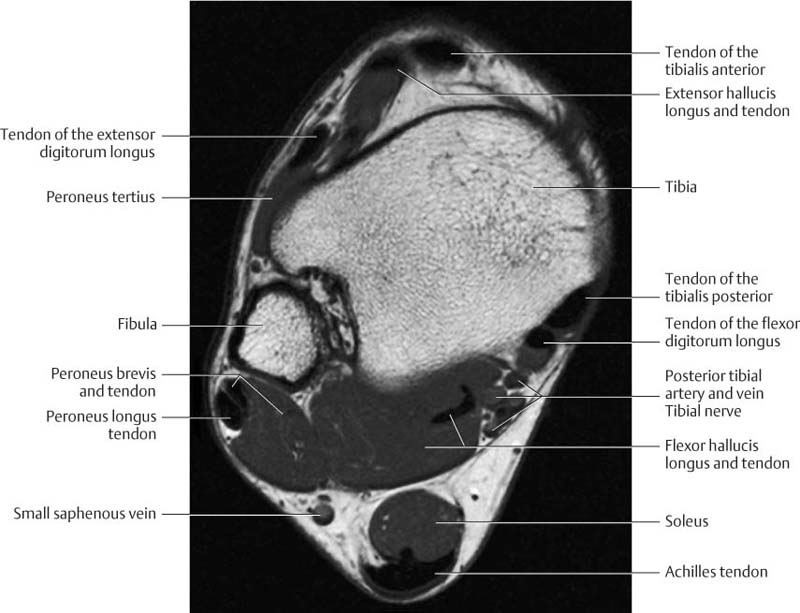

Normal Magnetic Resonance Imaging Anatomy Of The Ankle & Foot

www.mri.theclinics.com

www.mri.theclinics.com

ankle anatomy foot mri normal coronal resonance imaging t1 magnetic fig

Normal Magnetic Resonance Imaging Anatomy Of The Ankle & Foot

www.mri.theclinics.com

www.mri.theclinics.com

mri anatomy foot ankle normal plantar muscle tissue resonance magnetic imaging res hi soft gr10